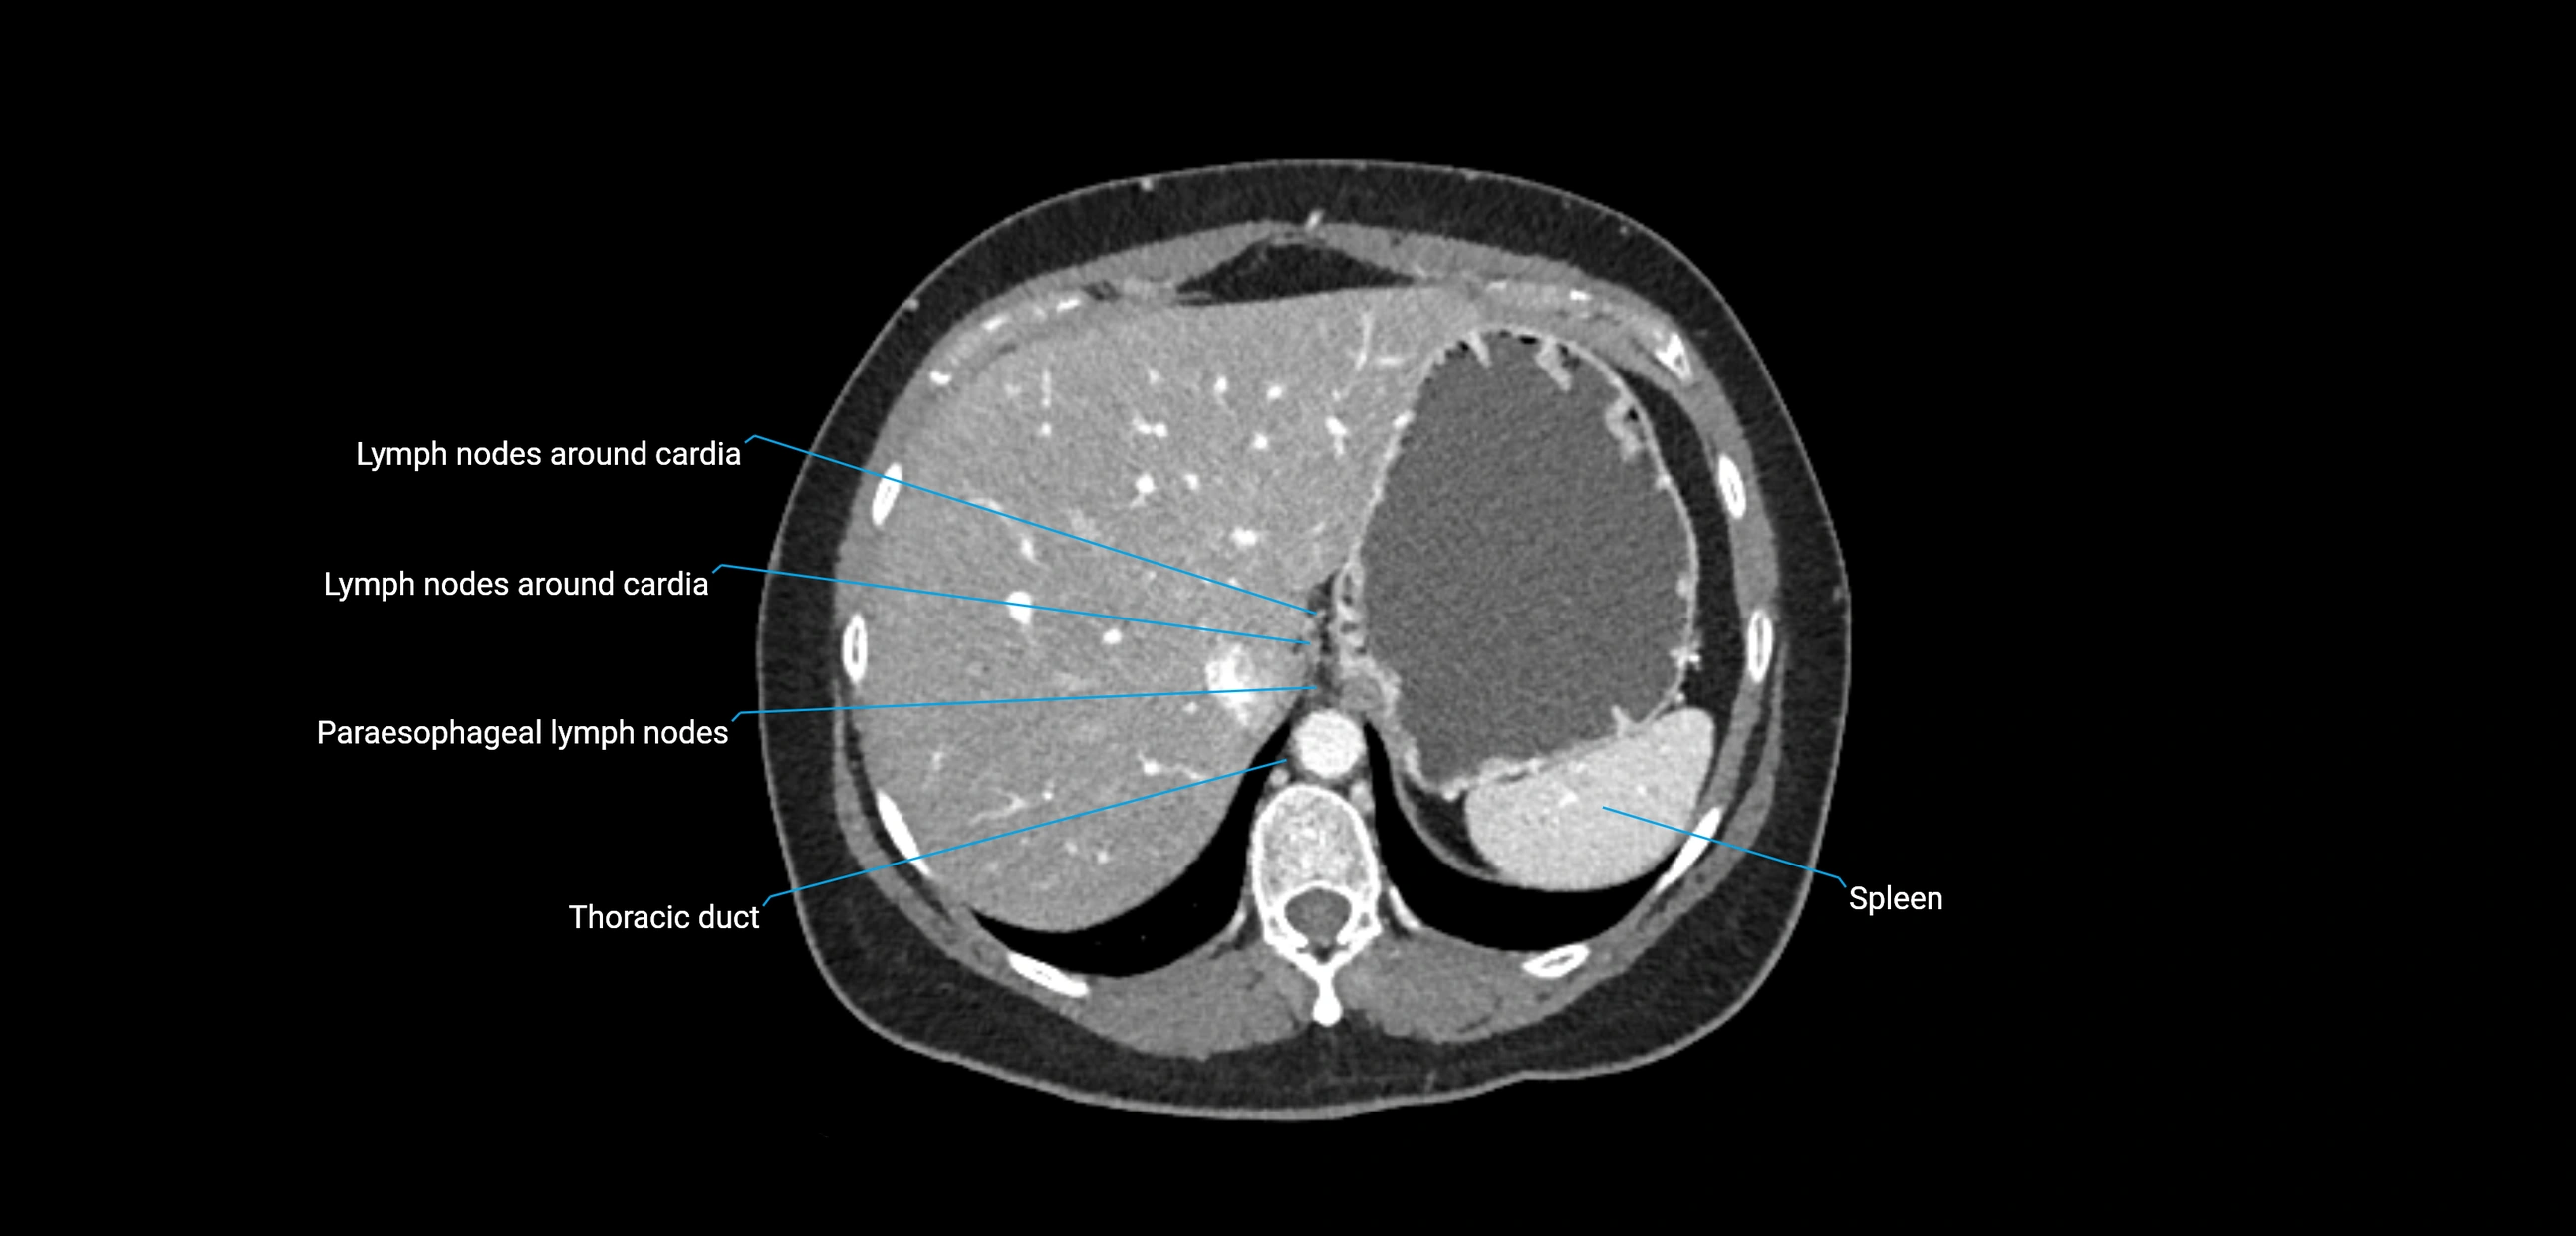

CT Appearance

CT Pre-Contrast:

• Nodes appear as soft-tissue density nodules adjacent to the aorta and IVC

• Calcification may be seen in chronic infections (e.g., tuberculosis)

CT Post-Contrast:

• Normal nodes enhance homogeneously

• Malignant nodes may show heterogeneous enhancement, central necrosis, or conglomerate formation

• Size >1 cm short axis is suspicious, though morphology and distribution are equally important